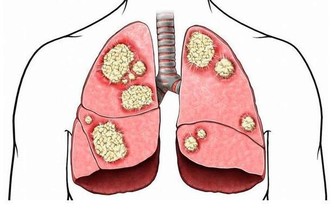

4、肺

每個人有左右兩個肺,但是肺是不可以捐贈的,

捐了一個肺之後,剩下的肺不能維持人體的呼吸功能。